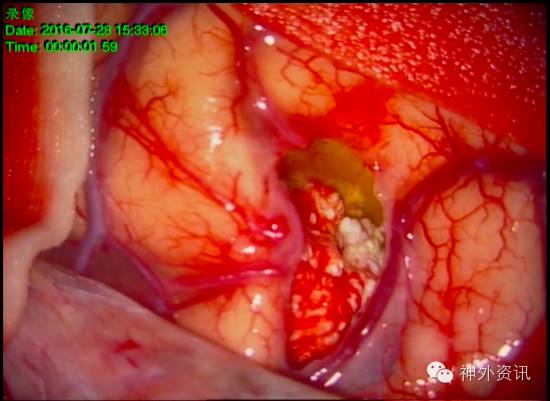

经术前科室讨论,认为患者左额顶叶病灶与临床症状有关联,病灶周围水肿明显,高级别胶质瘤可能。有明确手术指征。完善术前检查后,全麻下行开颅右侧额顶叶肿瘤切除术。术中见肿瘤上方淡黄色囊液,肿瘤呈乳白色,边界清楚,质地硬,血供一般,与周围组织粘连明显(图2)。显微镜下全切肿瘤,手术顺利。

图2. 术中见右额顶叶皮质下白色钙化状肿块,前部为淡黄色囊液。